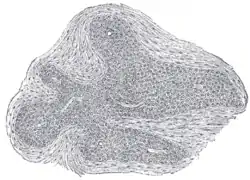

Section of an irregular nodule of the glomus coccygeum. X 85. The section shows the fibrous covering of the nodule, the bloodvessels within it, and the epithelial cells of which it is constituted.

It is about 2.5 mm. in diameter and is irregularly oval in shape; several smaller nodules are found around or near the main mass.

It consists of irregular masses of round or polyhedral cells epitheloid cells, which are grouped around a dilated sinusoidal capillary vessel.